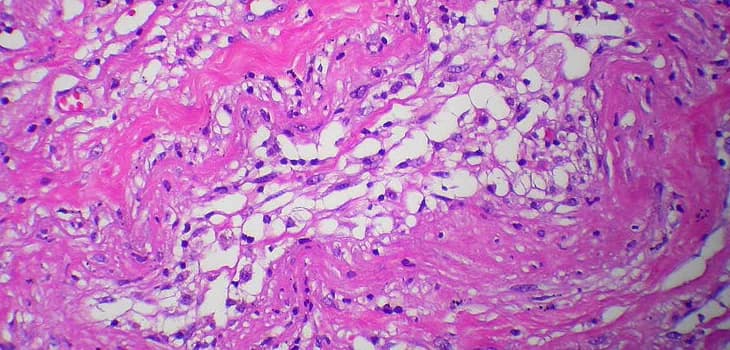

Lipogems® Orthopedic treatment utilizes your body's own adipose tissue to address various musculoskeletal issues. This minimally invasive procedure harnesses the regenerative properties of fat cells to promote healing and reduce pain in joints, tendons, and bones. The treatment offers a natural alternative for patients seeking to improve mobility and quality of life without resorting to major surgery.

Joint pathologies such as osteoarthritis limit the quality of life for millions of people. Regenerative medicine has revolutionized therapeutic approaches, and Lipogems has emerged as a true game changer, offering an effective solution that reduces pain, improves mobility, counteracts inflammation, and promotes tissue regeneration.

Hundreds of studies and scientific publications have demonstrated that treatment with Lipogems provides significant benefits for patients with osteoarthritis, delivering longer-lasting results compared to traditional drug-based therapies. When combined with arthroscopy, it has also shown positive effects for several years after treatment, improving joint function.

Lipogems has proven effective in treating knee, hip, shoulder, and ankle osteoarthritis, as well as tendinopathies, cartilage lesions, thumb basal joint arthritis, and carpal tunnel syndrome. Its ability to reduce inflammation and stimulate tissue regeneration makes it one of the most promising solutions for those seeking a non-invasive alternative to traditional surgery.